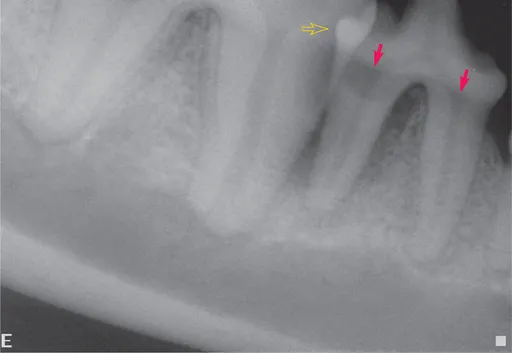

FIGURE 1-1 Structures that are radiolucent subtract radiodensity from superimposed structures, making them seem to disappear due to the summation effect. In this radiograph, the radiolucent regions on the roots of the fourth premolar and first molar teeth just below the crowns (arrows) are not defects in the teeth. They are caused by lack of overlying alveolar bone apically and enamel coronally. Conversely, when radiodense structures are superimposed across a relatively radiolucent structure, they can seem to appear from a void. In this case, the overlapping contact surfaces of the fourth premolar and first molar tooth allow visualization of the distal aspect of the premolar tooth (open arrow).